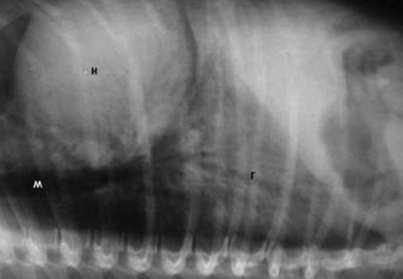

)        при рентгенологічному дослідженні (малюнок 1) в початкових стадіях бронхопневмонії у краніальних і серцевих долях реєструють гомогенні вогнища затемнення помірної щільності, розмитість легеневого малюнка в ділянці сегментів чи всього легеневого поля, завуальованість переднього контуру серця, нечіткість контурів бронхіального дерева.

Малюнок 1. Рентгенограма органів грудної клітки собаки у бічній проекції - ознаки бронхопневмонії

При рентгенологічному дослідженні в початкових стадіях бронхопневмонії у краніальних і серцевих долях реєструють гомогенні вогнища затемнення помірної щільності, розмитість легеневого малюнка в ділянці сегментів чи всього легеневого поля, завуальованість переднього контуру серця, нечіткість контурів бронхіального дерева.